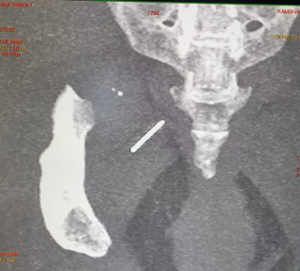

At Sir Ganga Ram Hospital, Rambha underwent imaging with an X-ray and CT scan pre-operatively.

“After taking the incision and starting dissection, it was very difficult to locate the needle. Multiple X-rays had to be taken intraoperatively to precisely locate the needle, and finally, the team found the needle and extracted it in one piece without breaking it. It was a highly complex task,” said Tarun Mittal, Senior Consultant in Dept of General Surgery at the hospital.